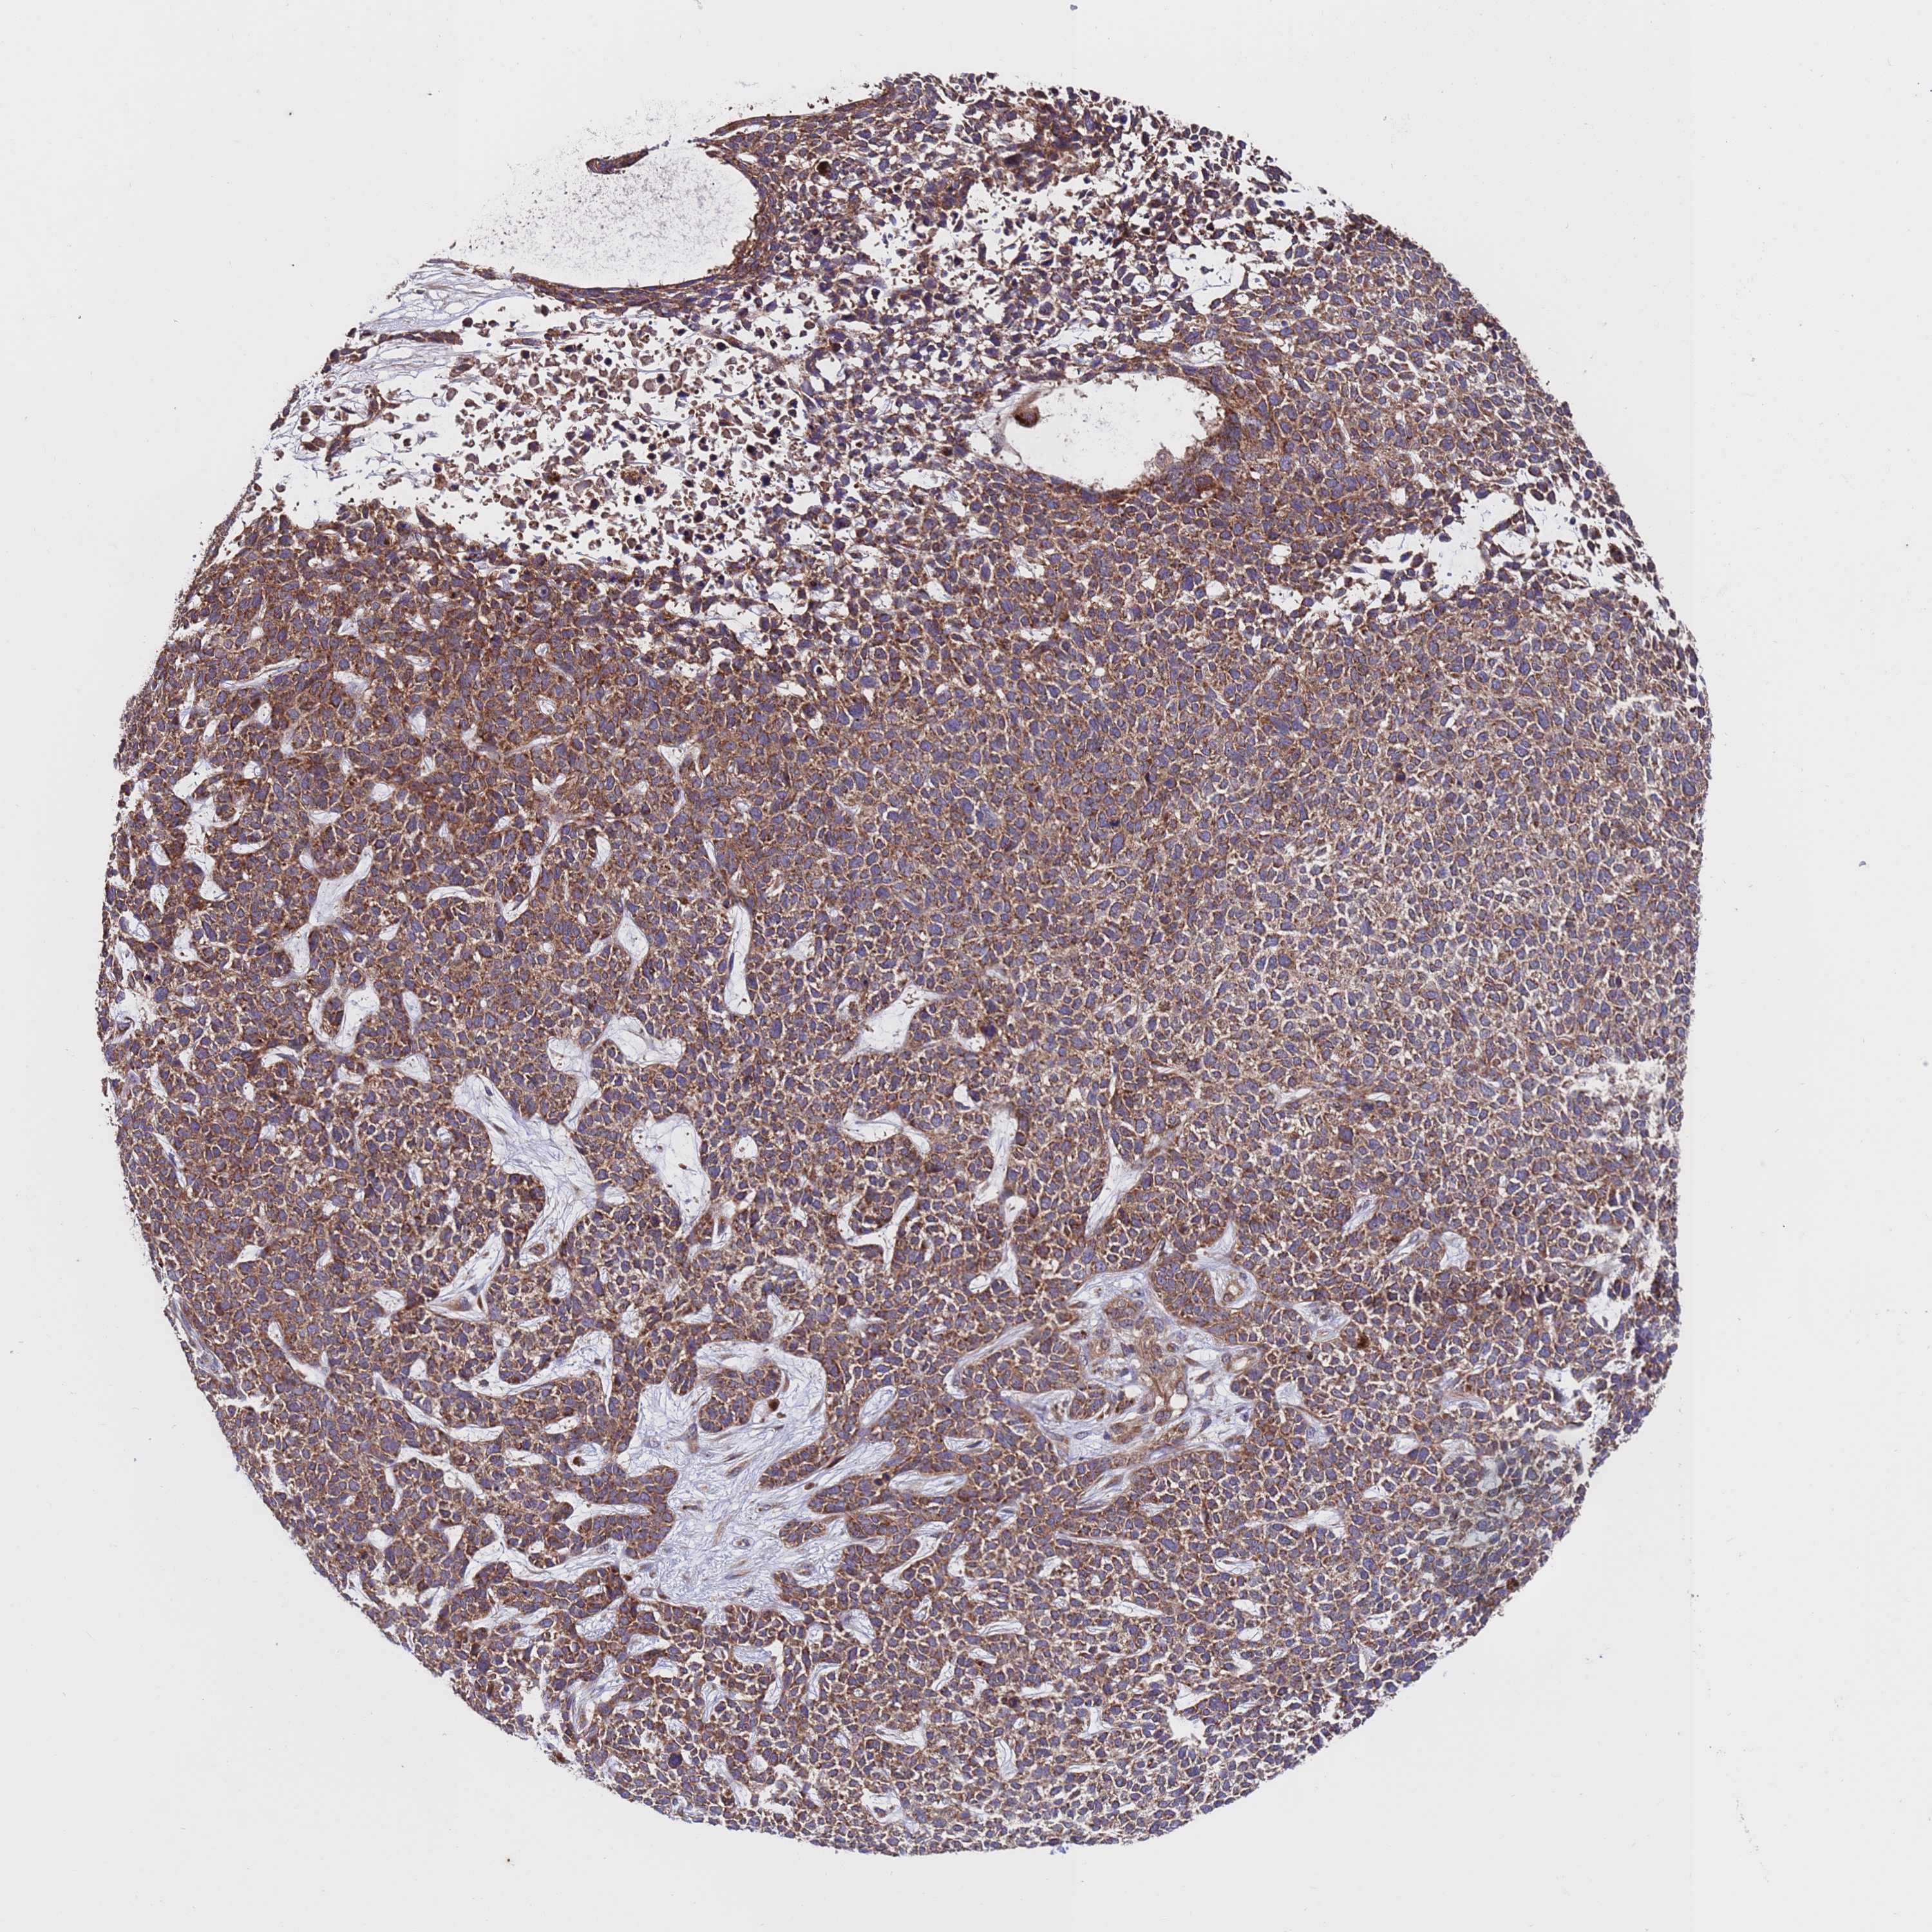

SKIN CANCER - Protein expressioni

A mouse-over function shows sample information and annotation data. Click on an image to view it in a full screen mode. Samples can be filtered based on level of antibody staining by selecting one or several of the following categories: high, medium, low and not detected. The assay and annotation is described here.

Antibody stainingi

Antibody staining in the annotated cell types in the current human tissue is reported as not detected, low, medium, or high, based on conventional immunohistochemistry profiling in selected tissues. This score is based on the combination of the staining intensity and fraction of stained cells.

Each image is clickable and will lead to virtual microscopy that enables deeper exploration of all samples and also displays staining intensity scores, fraction scores and subcellular localization as well as patient and tissue information for each sample.

Antibody HPA046265

Staining

High

Medium

Low

Not detected

Intensity

Strong

Moderate

Weak

Negative

Quantity

>75%

75%-25%

<25%

None

Location

Nuclear

Cytoplasmic/membranous

Cytoplasmic/membranous,nuclear

Squamous cell carcinoma, NOS